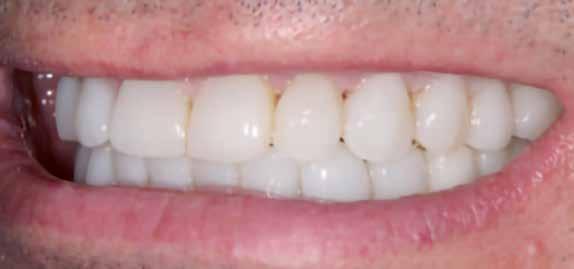

A fogkontúrálás és az interproximális redukció alkalmazásával a mikroesztétikai részletek tökéletesítése is megtörtént (11. kép) A kezelés mindössze 16 hónapig tartott, megtörtént a rágófunkció helyreállítása, és az esztétikai végeredmény sokéves várakozás után valóban fordulópontot jelentett páciensünk életében (12-14. képek).

A fogszabályozás aktív fázisa után minden kezelésnél a retenció, a passzív helyben tartó fázis legalább annyira fontos, mint az előtte történtek, továbbá a fogak pozíciójának, de a beállított harapás stabilitásának a segítése is.

Előbbi elérésében az ún. essix retainerek, az egy fogívre kiterjedő mélyhúzott sínek tartják a felső és alsó fogívben a fogakat a beállított pozíciójukban, a felső és alsó frontfogakra orálisan ragasztott fix retainerek mellett (15. kép).

A harapás sagittális rögzítésében elengedhetetlen szerepe van az ún. Pitts Izom Tréning Splintnek, amelyben a páciens összeharap, így az megakadályozza az alsó fogsor visszamozdulását a disztálharapásos helyzetbe (16. kép).